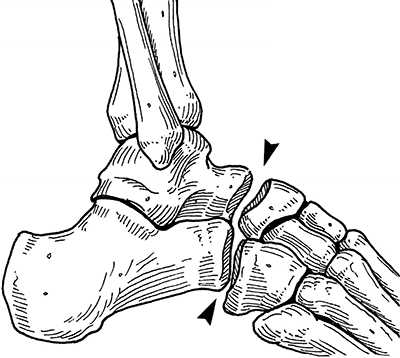

Анатомия повреждения сустава Лисфранка.

Выделяют такие анатомические структуры как связка Лисфранка, сустав Лисфранка и суставной комплекс Лисфранка. Суставной комплекс Лисфранка состоит из предплюсне-плюсневых суставов, межплюсневых суставов, межпредплюсневых суставов.

Наиболее важным моментом в понимании повреждений сустава Лисфранка является осознание критической роли связки Лисфранка в стабилизации не только второго предплюсне-плюсневого сустава но и поддержке всего подошвенного свода. Связка Лисфранка состоит из трёх пучков и связывает медиальную клиновидную кость с основанием второй плюсневой кости. Связка Лисфранка препятствует избыточной пронации и абдукции стопы.

В образовании суставного комплекса Лисфранка также участвуют подошвенные предплюсне-плюсневые связки, тыльные предплюсне-плюсневые связки, межпредплюсневые связки.

За счёт большого количества связок и особенностей строения суставов, суставной комплекс Лисфранка является крайне стабильным с небольшой амплитудой движений.

При рентгенографии все снимки выполняются в сравнении со здоровой стопой. Существует несколько основных рентгенологических признаков повреждения сустава Лисфранка. 1. Отсутствие параллельности медиального края основания 2-й плюсневой и медиального края медиальной клиновидной кости 2. Расширение между основаниями 1 и 2 плюсневых костей 3. Наличие костного фрагмента в области основания 2-1 плюсневой кости 4. Тыльный подвывих на боковой проекции 5. Разрыв линии предплюсне-плюсневого сочленения.

Вершиной, ключом, блокирующим клином - в общем главной частью сустава Лисфранка является 2 плюсне-клиновидный сустав. По этой причине мы предпочитаем начинать фиксацию именно с него. Для артродеза используем винты с направленной в разные стороны резьбой FT Arthrex диаметром 4 мм. Они позволяют создать мощную межфрагментарную компрессию, а за счёт глубокой резьбы очень надёжно фиксируются в кости.